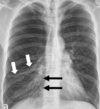

Derrame pleural

Líquido en espacio pleural

154

Rx derrame pleural

* Borramiento de ángulos * Masivo = empuja

155